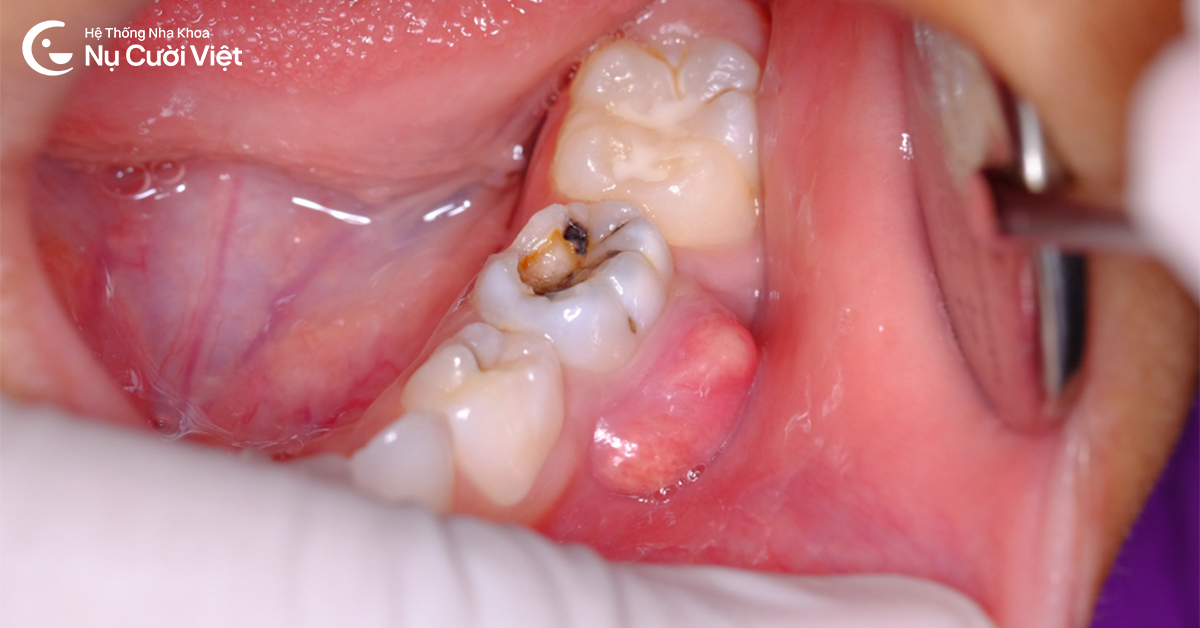

Sâu răng lâu ngày không được điều trị khiến tủy răng nhiễm trùng, gây sưng nướu răng có mủ

Áp xe răng và sâu răng nặng: Vi khuẩn tấn công vào tủy răng tạo ra các túi mủ ở vùng chóp chân răng, khiến nướu sưng to, đau nhức dữ dội và có thể gây sưng cả vùng má.